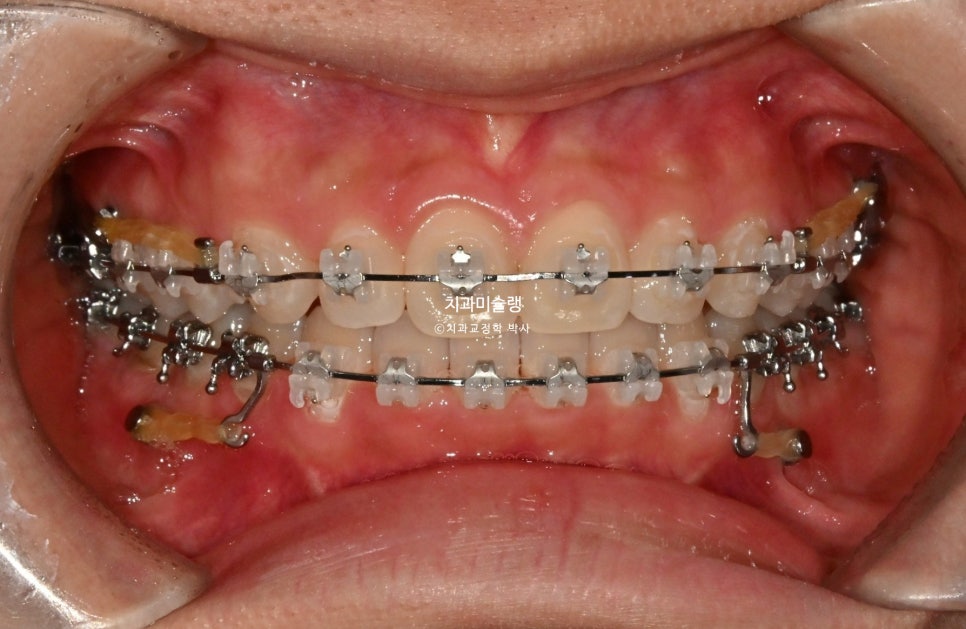

2026년 1월 – 치료 시작 1년차

치료 시작 1년차 모습입니다. 치료 도중 턱관절 불편감은 딱히 없었습니다. 인비절라인에서 클리피씨로 바꿨기 때문에 턱관절이 편해진건 아닙니다. 앞니 과개교합으로 인한 조기접촉을 초기에 먼저 해결했기 때문이죠. 고정용 나사를 4군데 심고 전체치열을 뒤로 당기고 있습니다.

본원의 치료계획은 지난 4월 본원에 처음 왔을때와 동일하게 교정용 나사를 4군데 심고 전체 치열을 사랑니 공간으로 후방이동 하는 비발치 돌출입 교정입니다. 인비절라인도 가능하나, 환자분은 재교정에 인비절라인을 다시하기 보다는 클리피씨를 선택하셨고 2025년 1월, 치료에 들어갔습니다.